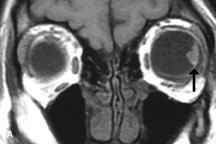

Lymphomas have MRI characteristics similar to those of inflammatory lesions in that they are hypointense to fat and isointense to muscle on T1-weighted images (Fig. 22). They may appear hyperintense to fat on T2-weighted images, perhaps owing to less fibrosis than that seen in orbital inflammatory pseudotumor, although this is not a consistent finding.31,50,66 Lymphoid tumors typically enhance moderately after contrast injection. Unfortunately, studies have shown that tumor density and homogeneity are similar between inflammatory and malignant orbital infiltrates, and MRI cannot differentiate these lesions.72,73

Fig. 22. A and B. T1- and (C) T2-weighted MR scans demonstrate a poorly defined multicompartmental mass enveloping the lateral rectus, superior rectus, and levator palpebrac superioris muscles. The lesion is isointense to brain on T1- and T2-weighted scans, as is typical for highly cellular neoplasms. D. Postcontrast fat-suppressed T1-weighted scan demonstrates intense enhancement of the infiltrating intraconal and extraconal tumor.